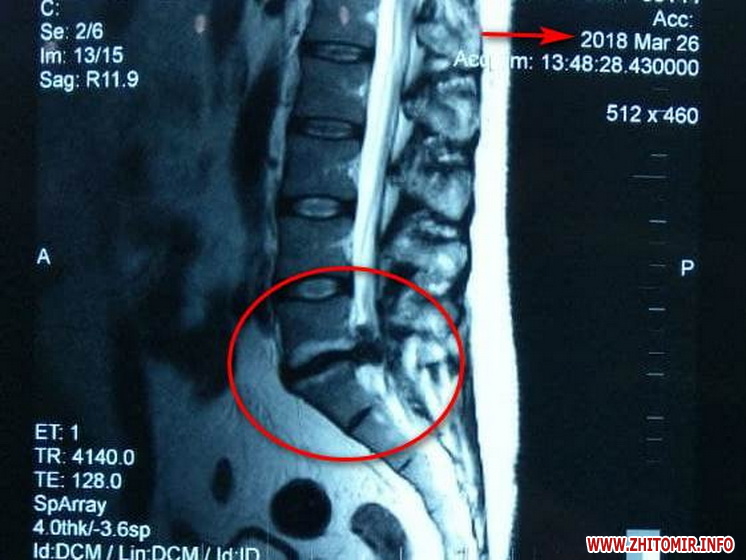

Нещодавно до мене прийшов мій пацієнт на повторний огляд, у якого у 2018 році була діагностована секвестрована кила хребта, яка підлягала оперативному втручанню. Медикаментозне лікування не приносило полегшення. Ми підібрали йому курс комплексного лікування на 20 днів. Повторне МРТ показало, що кила зникла, лишилася лише протрузія, яку ми також успішно пролікували», - розповідає Валентина Яцук, лікар вертебролог центру.